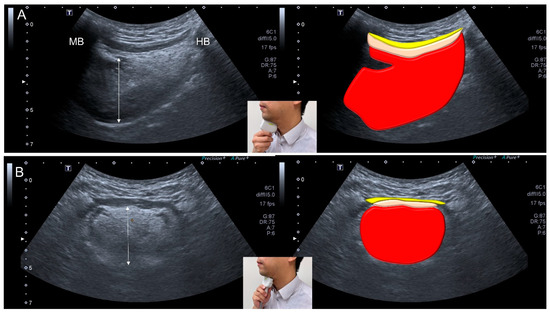

- Ogawa, N.; Mori, T.; Fujishima, I.; Wakabayashi, H.; Itoda, M.; Kunieda, K.; Shigematsu, T.; Nishioka, S.; Tohara, H.; Yamada, M.; et al. Ultrasonography to Measure Swallowing Muscle Mass and Quality in Older Patients With Sarcopenic Dysphagia. J. Am. Med. Dir. Assoc. 2018, 19, 516–522. [Google Scholar] [CrossRef]

- Mori, T.; Wakabayashi, H.; Ogawa, N.; Fujishima, I.; Oshima, F.; Itoda, M.; Kunieda, K.; Shigematsu, T.; Nishioka, S.; Tohara, H.; et al. The Mass of Geniohyoid Muscle Is Associated with Maximum Tongue Pressure and Tongue Area in Patients with Sarcopenic Dysphagia. J. Nutr. Health Aging 2021, 25, 356–360. [Google Scholar] [CrossRef] [PubMed]

- Ogawa, N.; Wakabayashi, H.; Mori, T.; Fujishima, I.; Oshima, F.; Itoda, M.; Kunieda, K.; Shigematsu, T.; Nishioka, S.; Tohara, H.; et al. Digastric muscle mass and intensity in older patients with sarcopenic dysphagia by ultrasonography. Geriatr. Gerontol. Int. 2021, 21, 14–19. [Google Scholar] [CrossRef] [PubMed]

| Ultrasonography | <1536 mm2 for the cross-sectional area of the tongue muscle <75.1 mm2 for the cross-sectional area of the digastric muscle |